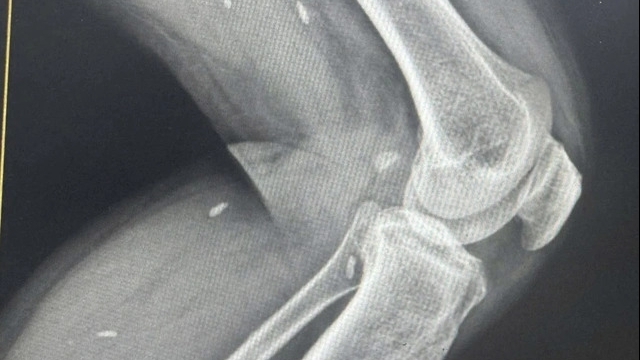

Được biết thanh niên này có tiền sử hút thuốc lá 5 năm. Trước lúc vào viện 2 giờ, người bệnh đột ngột đau tức ngực trái và khó thở. Các Bác sĩ chỉ định cho thanh niên này đi chụp phim cắt lớp vi tính lồng ngực, kết quả cho thấy bệnh nhân bị tràn khí, tràn dịch màng phổi trái.

Sau khi hội chẩn, các bác sỹ đã quyết định phẫu thuật dẫn lưu màng phổi trái cấp cứu, hút ra khoảng 600ml máu không đông và khí. Bệnh nhân được dùng thuốc cầm máu và theo dõi dẫn lưu màng phổi. Sau 12 giờ, các bác sỹ đã tiến hành phẫu thuật nội soi cầm máu, đốt kén khí và gây dính màng phổi cho người bệnh.

BS Hải cho biết, đây là một ca bệnh đặc biệt, rất hiếm gặp, người bệnh có tràn khí màng phổi tự phát gây xẹp phổi co kéo dẫn đến đứt dây chằng đỉnh phổi chảy máu vào khoang màng phổi.

Trong trường hợp này, nếu không được xử lý kịp thời người bệnh có thể nguy hiểm đến tính mạng do sốc mất máu, tràn máu tràn khí màng phổi gây chèn ép trung thất.